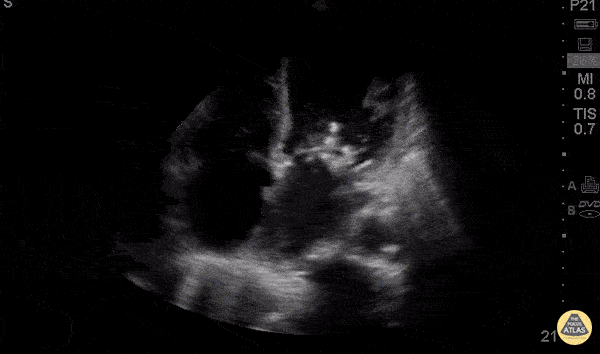

Valvulopathy - Mitral Vegetations

62 y/o M no PMH visiting from the Caribbean presents with 3 days of acute onset shortness of breath associated with severe exertional dyspnea, orthopnea and cough productive of whitish sputum without fevers or chest pain. POCUS was performed to evaluate undifferentiated shortness of breath. Subcostal view revealed vegetations on both mitral valve leaflets with severe mitral regurgitation, biatrial enlargement and global hypokinesis. Acute onset of severe heart failure requires emergent surgical intervention including mitral valve repair vs replacement. In our patient, POCUS lead to emergent transfer for CT surgery. Dr’s Karen Benabou, Eden Kim, and Eric Schnitzer - Kings County Emergency Medicine